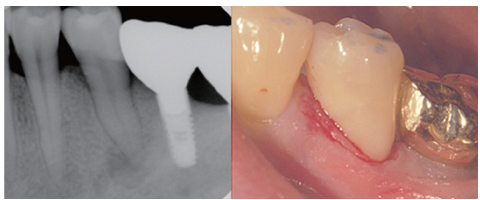

Figure 1

Preoperative periapical view and clinical photograph. (a) Periapical radiolucency on #35; (b) Cervical abrasion.

Figure 1 Preoperative periapical view and clinical photograph. (a) Periapical radiolucency on #35; (b) Cervical abrasion.